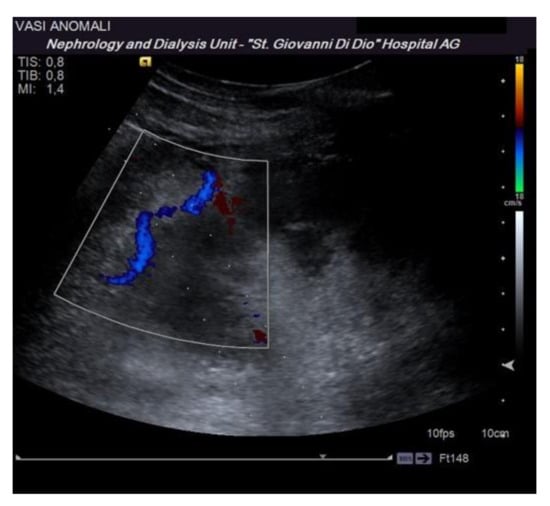

Before performing an ultrasound-guided PRB, it is advisable to perform a complete ultrasound examination of the kidneys in the same position as the procedure to evaluate the location of the kidney, its excursion during breathing, the cortical thickness, and the distance of the kidney from the skin surface. These data are useful to plan the procedure. Furthermore, this allows for the exclusion of anatomical variants (for example, horseshoe kidney), hydronephrosis, and cystic lesions, which may be contraindications for the procedure [16]. The examination must be completed with an ECD assessment to rule out the presence of vessels along the presumed path of the needle (Figure 3). Vascular abnormalities are reported in up to 10% of patients who undergo renal biopsy, and this may explain the reduction in complications observed when an ECD study preceded the procedure [15].

Figure 3.

The dotted lines show the expected trajectory of the needle when correctly fixed to the appropriate support. At the lower pole of the kidney, the site of the biopsy, there is an abnormal vascular formation that would have been crossed by the needle if it had not been recognized.

A solitary kidney is considered a relative contraindication to PRB by some authors. In reality, there is no evidence in the literature of a significantly higher number of complications in this population, and fear in this sense is not justifiable. In patients with renal dysmorphism, in particular, in the so-called horseshoe kidney situation, particular attention must be paid to possible associated vascular anomalies. Since abnormal vessels could be in the path of the needle, it is mandatory to perform an ECD examination during the procedure [16].